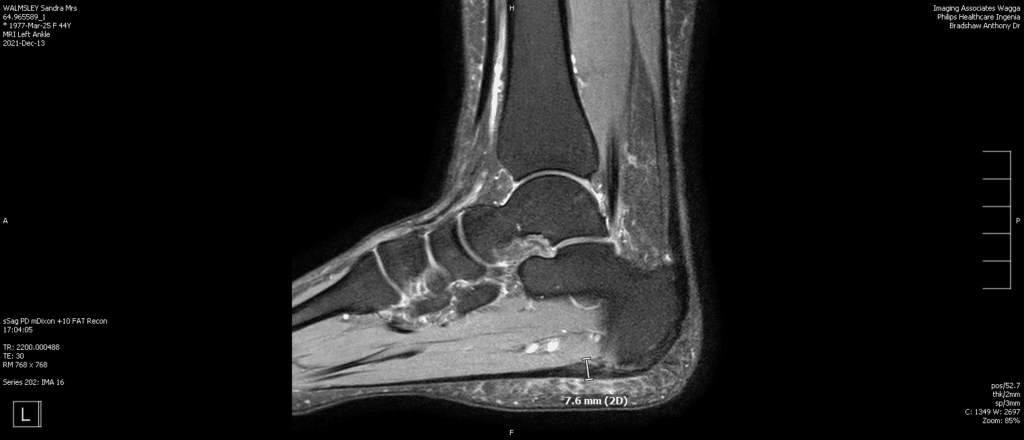

Plantar fasciitis is an inflammation of the origin of the fascia at the calcaneus (heel bone). It is a result of a repetitive strain/tear and repair of the fascia from traction forces that have worn it out. It can be likened to an elastic band that has been left out in the sun and stretched too many times; it looses its stretch and has many micro-tears in it.

Heel spurs have long been associated with heel pain, and were originally thought to be its cause. Heel spurs occur at the origin of the flexor digitorum brevis muscle, which lies just beneath  the plantar fascia. However, heel spurs are not often the cause of heel pain associated with plantar fasciitis but can be locally inflamed or even fracture.